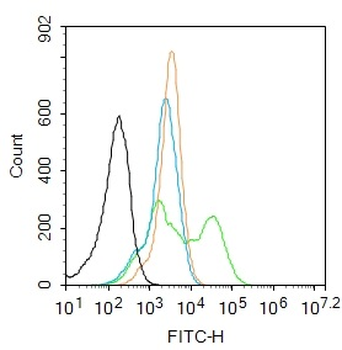

Phospho-CDKN1A/p21 (Thr145) Rabbit Polyclonal Antibody [orb6568]

FC, IF, IHC-Fr, IHC-P

Mouse, Rat

Human, Mouse, Rat

Rabbit

Polyclonal

Unconjugated

100 μl, 50 μl, 200 μlPhospho-CDKN1A/p21 (Ser130) Rabbit Polyclonal Antibody [orb6571]